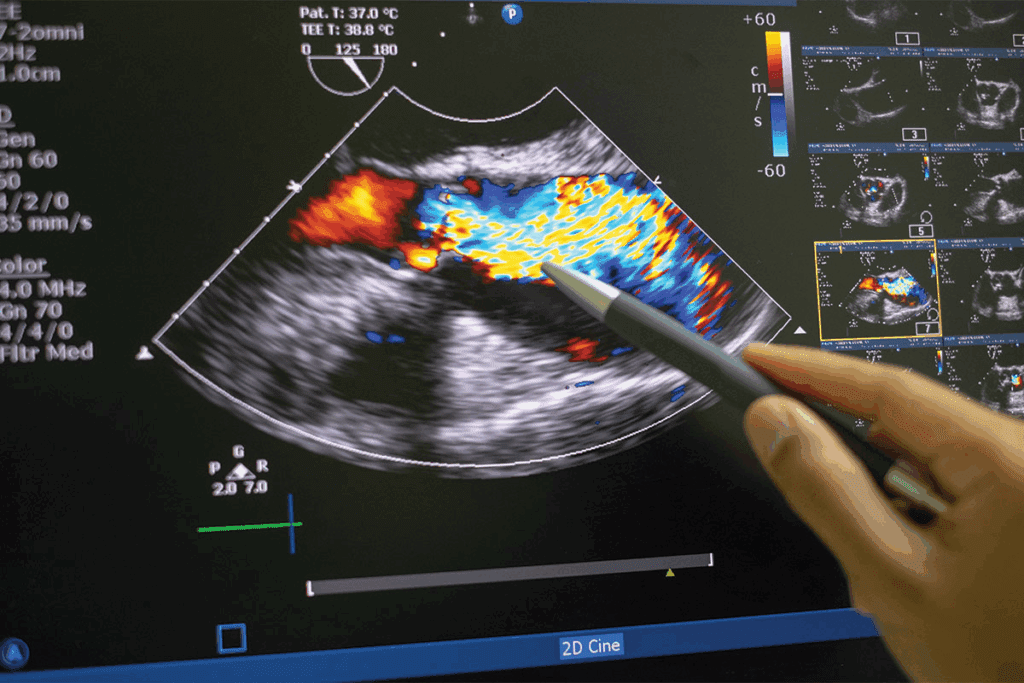

The Role of Ultrasound in Pregnancy Monitoring

Ultrasound is a big help in keeping an eye on a pregnancy. It lets doctors see the fetus and measure its growth. Fetal biometry looks at different parts of the fetus, like the head, belly, and thigh, to guess the baby’s weight and check its development.

By using ultrasound, we can watch how a fetus grows and find any problems early. This helps doctors make the best choices for managing the pregnancy and step in if needed.